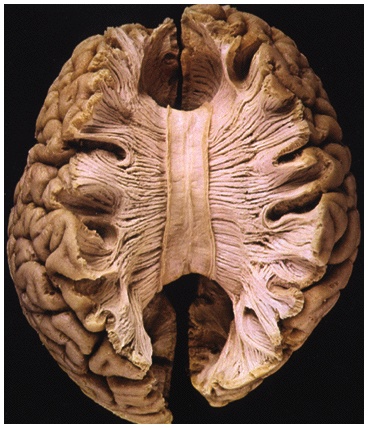

The Cerebral Cortex

• The intricate fabric of interconnected neural cells that covers the cerebral hemispheres. The body’s ultimate control and information processing center.

Structure of the Cortex

• Each brain hemisphere is divided into four lobes, separated by prominent fissures. They are frontal lobes (forehead), parietal lobes (top to rear head), occipital lobes (back head) and temporal lobes (side of head).